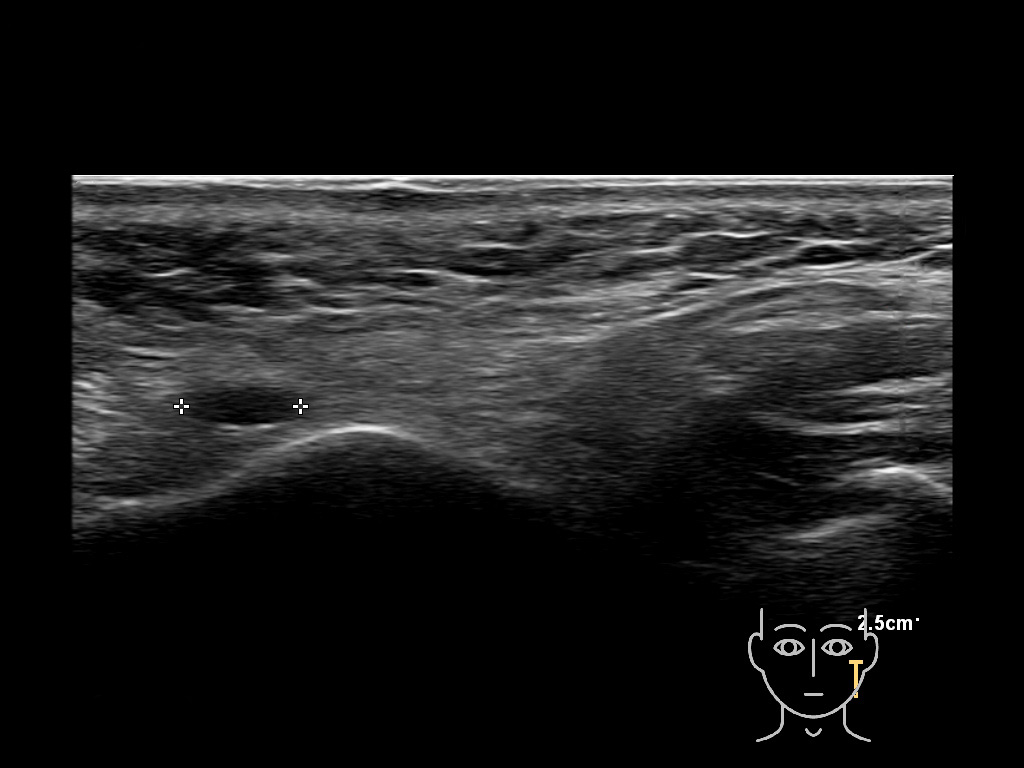

Parotid

Filler injections in the parotid gland may go unnoticed, however, inflammatory reactions and abscesses may occur. Hypervascularity can be seen with color doppler. Filler deposits are supposed to be injected into the superficial fatty layer . The space to inject into this layer may be limited. Routinely we measure a width of 2-4 millimeters with sometimes subcutaneous layers being less than one millimeter thick.

Study the first image to recognize the different layers. If you are sure about the layers, swipe to the second image to view the answer (if applicable).